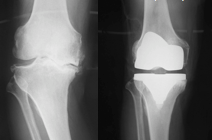

関節手術

X線写真(左:術前 右:術後)